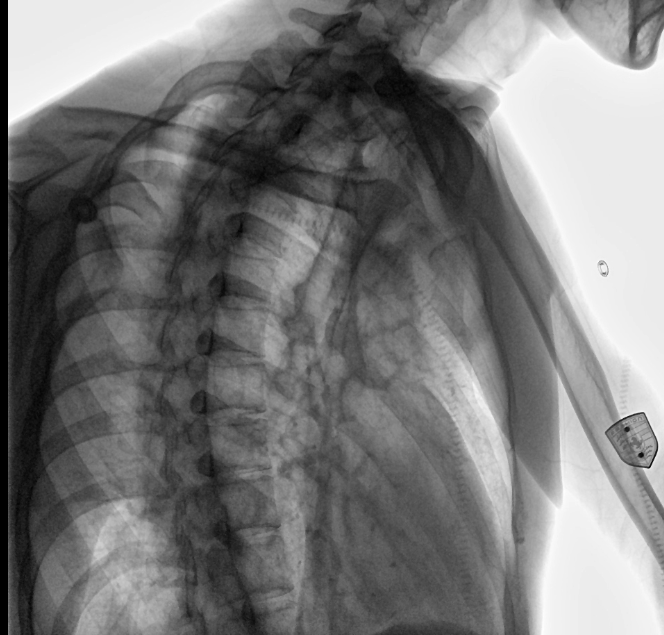

位于衡水市中醫(yī)醫(yī)院的動態(tài)平板數(shù)字化X射線系統(tǒng)DTP571具備高速高清點片功能。這是一款對放射科十分友好的產(chǎn)品。因為它把高速和高清點片結合,既能方便影像技師有效地抓拍需要的病灶的影像,又能給予影像醫(yī)生清晰的影像進行診斷。

動態(tài)觀察診斷,實時高清點片